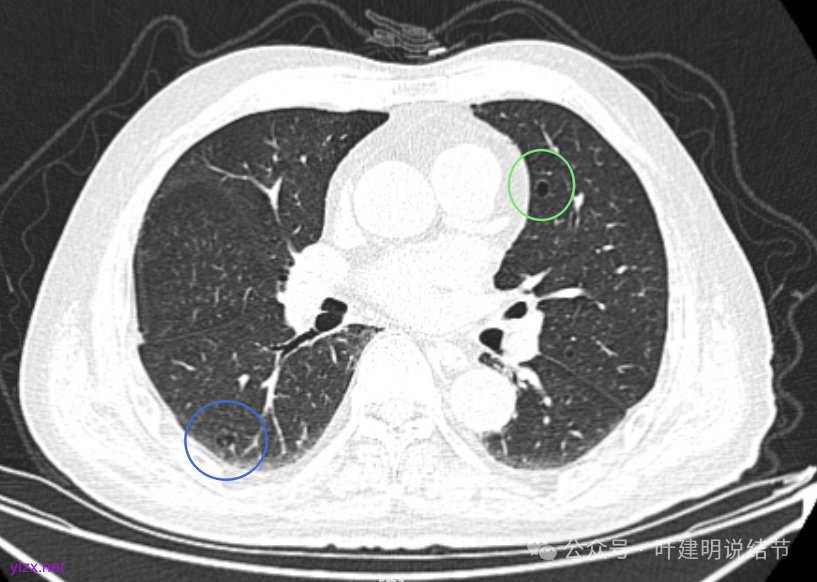

左肺上叶红色这处是囊腔型病灶,囊壁略不均,似有微小血管进入囊壁,对比2023年4月整个囊腔来讲有扩大,需要考虑囊腔型肺癌的可能性大。右侧蓝色的并不是典型囊腔型肺癌的表现,再加上两肺绿色这些慢支肺气肿与肺大泡的影像,右侧的就更加不确切,至少近期不能够考虑右侧也要开刀的事情。其实左侧的主病灶相对于其他表现更典型的囊腔型肺癌来说,由于囊壁密度偏高,也不是百分百必定是肺癌。我的想法还是先等脑梗情况稳定,并且间隔4~6个月复查病灶再有进展在考虑单孔胸腔镜下局部切除就可以。淋巴结可以考虑采样,但一般不至于阳性。破是不会切破的。消融不建议,囊腔灶更难通过穿刺获得病理依据,况且东西在边上,能局部楔切,当然首选手术。意见供参考!